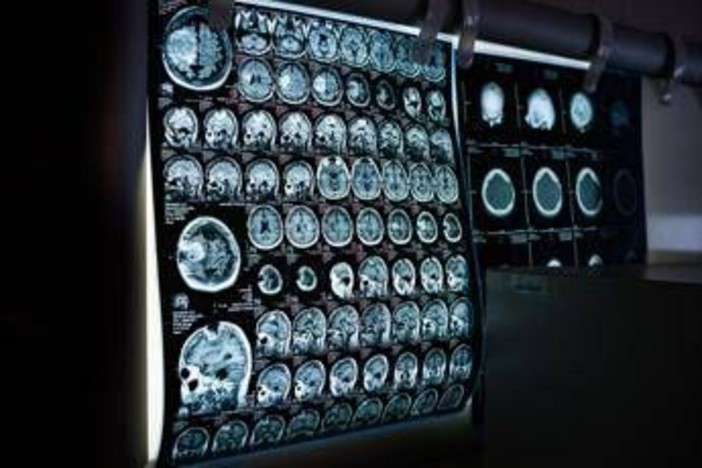

(Adnkronos) - In occasione della Giornata mondiale delle malattie rare 2026, che si celebra il 28 febbraio, la Società italiana di neurologia (Sin) rinnova il proprio impegno nel promuovere attenzione, consapevolezza e azioni concrete per i pazienti affetti da malattie neurologiche rare, un ambito che rappresenta una delle aree più complesse e in continua evoluzione. Queste patologie - informa la società scientifica in una nota - comprendono centinaia di condizioni differenti, spesso di origine genetica, che possono manifestarsi in età pediatrica o adulta e che sono frequentemente caratterizzate da un decorso progressivo e da un importante impatto funzionale. Nel loro insieme, queste patologie interessano un numero rilevante di persone e pongono sfide significative non solo sul piano clinico ma anche organizzativo, sociale ed economico, coinvolgendo l’intero sistema sanitario.

Un elemento centrale per migliorare la gestione delle malattie neurologiche rare - secondo gli esperti - è rappresentato dalla standardizzazione dei percorsi diagnostico-terapeutici, attraverso raccomandazioni condivise, algoritmi clinici e strumenti operativi che possano supportare il neurologo nella pratica quotidiana, anche al di fuori dei centri altamente specialistici. "Le malattie neurologiche rare, in particolare quelle di origine genetica, richiedono competenze specialistiche ma anche un approccio strutturato e condiviso”– sottolinea Massimiliano Filosto, coordinatore del Gruppo di studio Sin di Neurogenetica clinica e malattie rare - Il lavoro del Gruppo di studio è orientato alla definizione di best practices, allo sviluppo di algoritmi diagnostici e gestionali e alla formazione dei neurologi. Ridurre il ritardo diagnostico significa oggi offrire ai pazienti un accesso più tempestivo alle cure".

Negli ultimi anni, il panorama delle malattie neurologiche rare è stato profondamente trasformato dalla disponibilità di terapie innovative che stanno cambiando in modo concreto la storia naturale di alcune patologie. Tra queste rientrano, a titolo di esempio, le terapie enzimatiche sostitutive, le terapie di riduzione del substrato, gli oligonucleotidi antisenso, le terapie geniche e altre strategie avanzate attualmente in sviluppo clinico. Questi approcci terapeutici, già disponibili o in fase avanzata di sperimentazione per diverse condizioni neurologiche rare - illustrano i neurologi - rendono ancora più urgente una diagnosi tempestiva e una corretta stratificazione clinica dei pazienti. In molti casi, infatti, l’efficacia delle terapie è strettamente legata alla precocità dell’intervento e alla preservazione delle funzioni neurologiche residue.